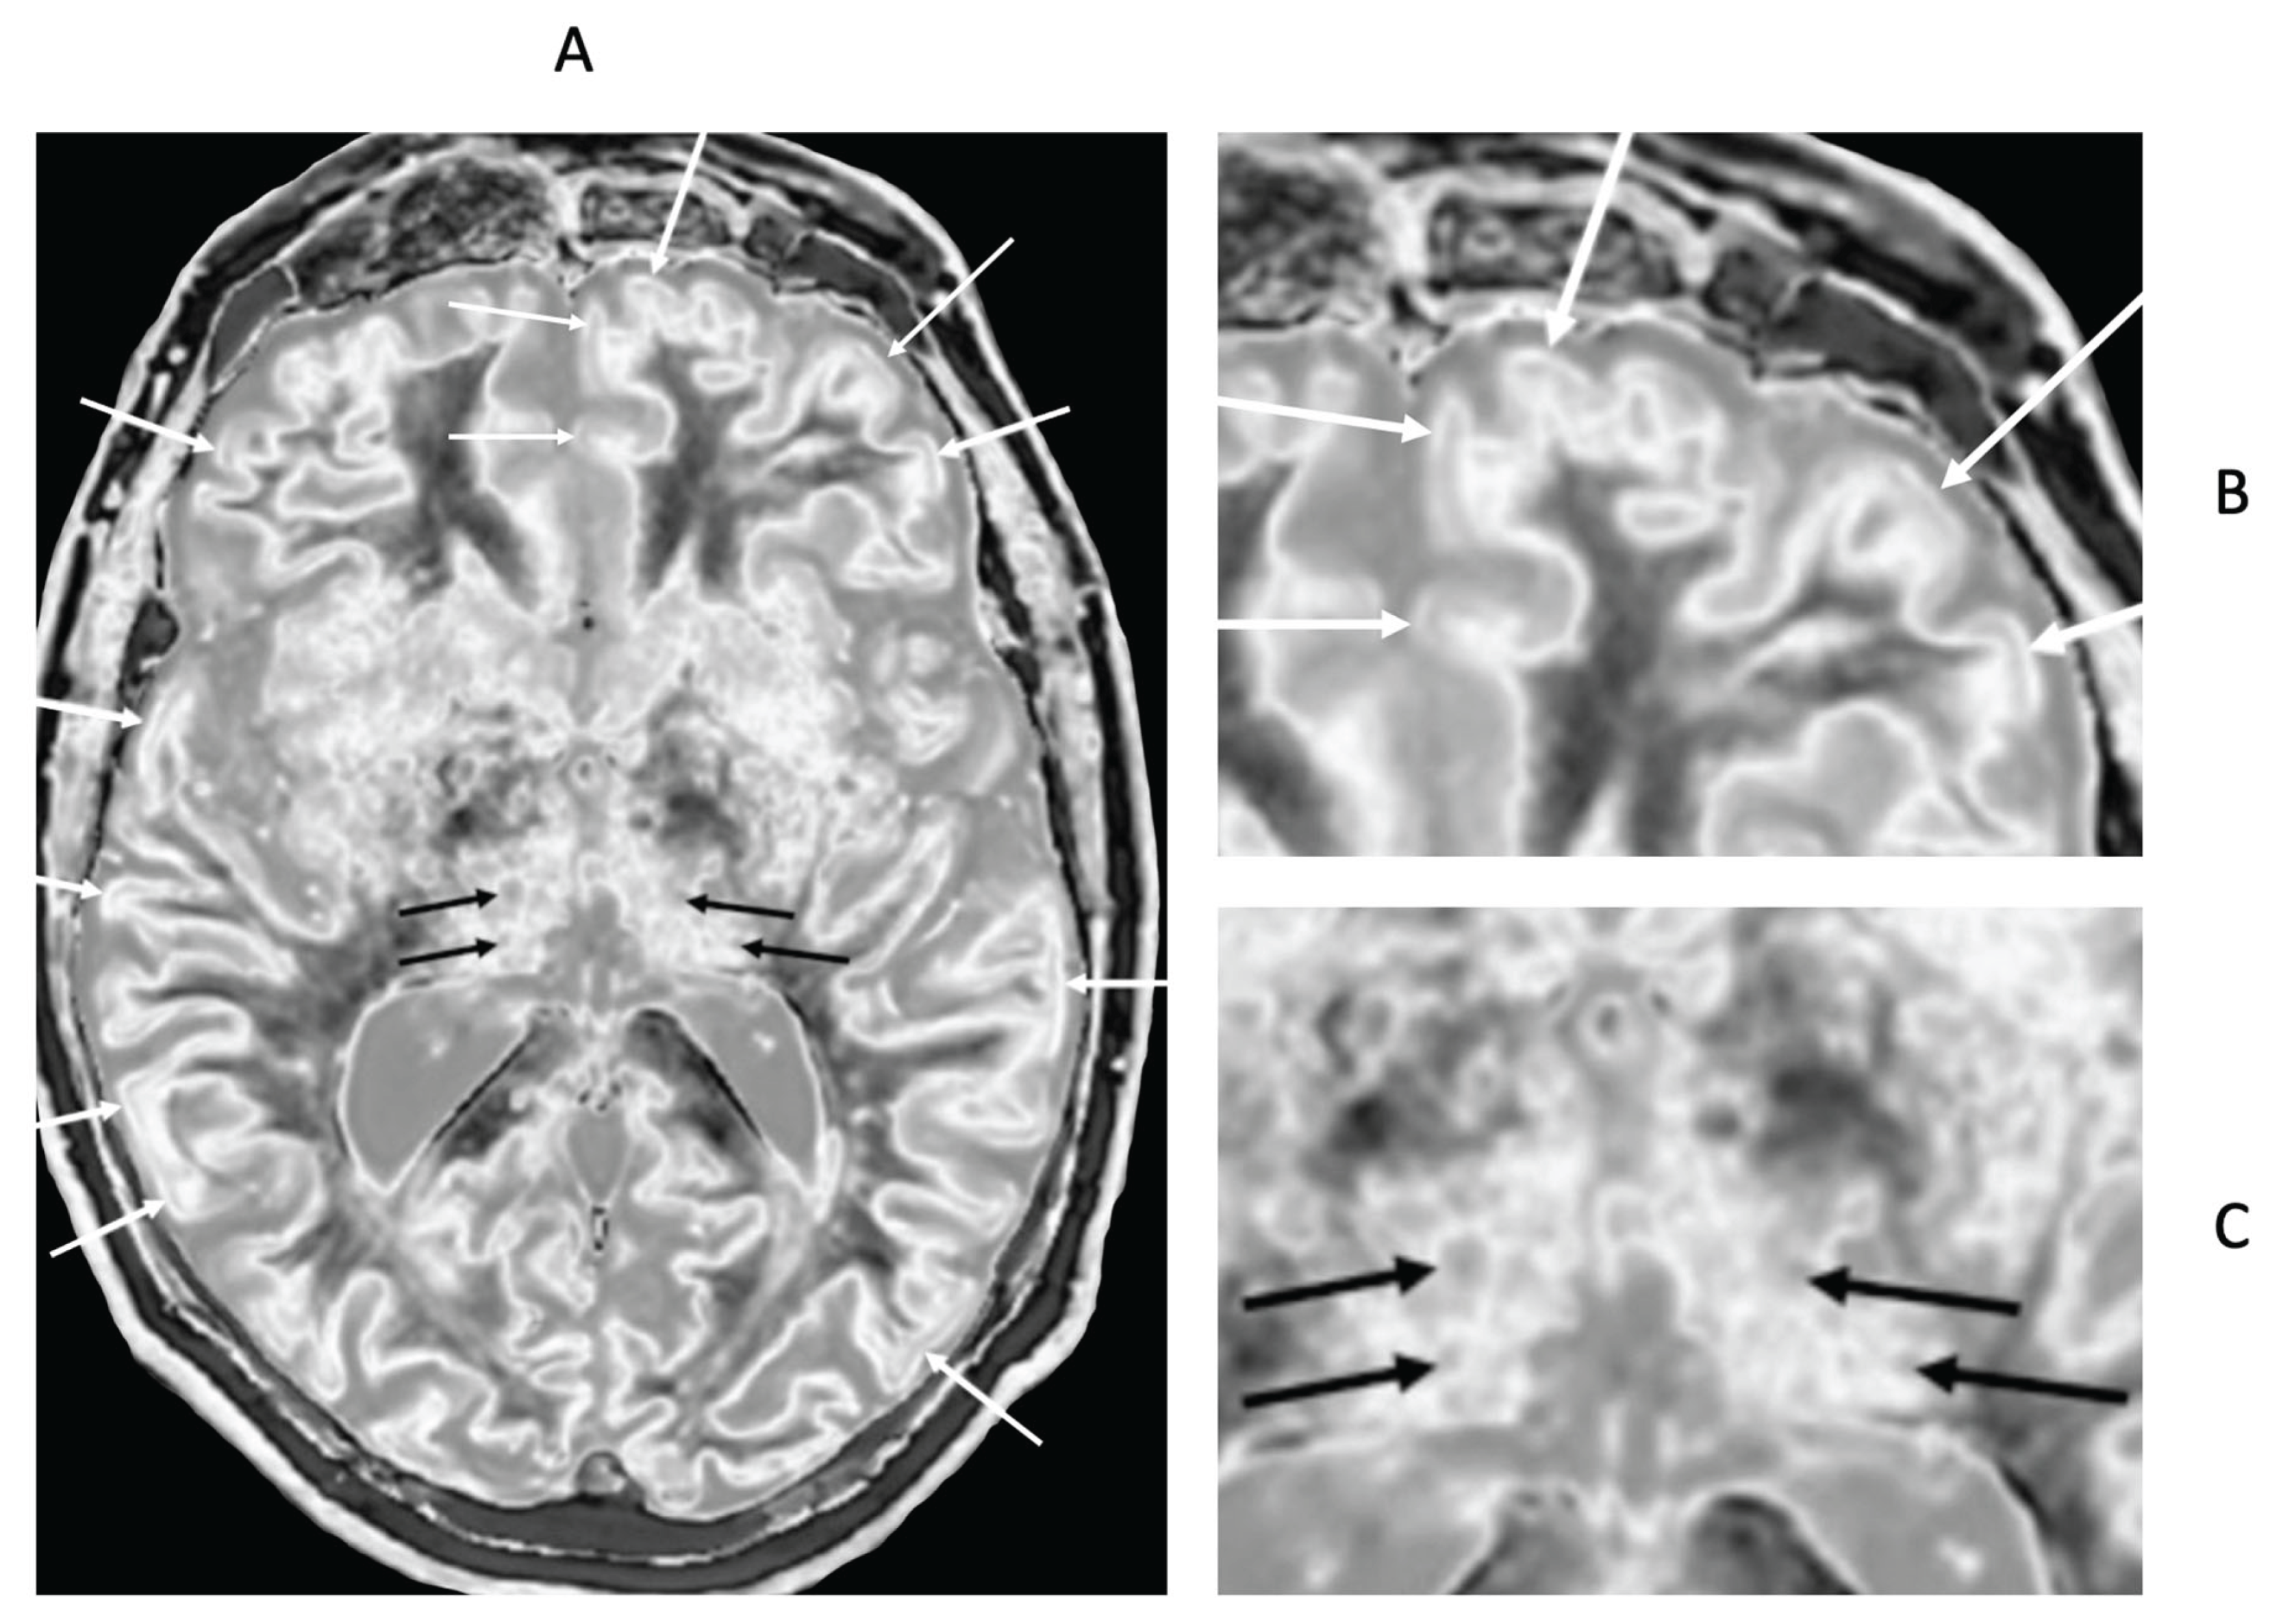

- Multiple Sclerosis (MS)

- Methamphetamine Substance Use Disorder

- Delayed Post-Hypoxic Leukoencephalopathy (Grinker’s Myelinopathy)

- Parkinson’s Disease

- Condron, P.; Cornfeld, D.M.; Scadeng, M.; Melzer, T.R.; Newburn, G.; Bydder, M.; Kwon, E.E.; McGeown, J.P.; Handsfield, G.G.; Emsden, T.; et al. Ultra-High Contrast MRI: The Whiteout Sign Shown with Divided Subtracted Inversion Recovery (dSIR) Sequences in Post-Insult Leukoencephalopathy Syndromes (PILS). Tomography 2024, 10, 983–1013. [Google Scholar] [CrossRef] [PubMed]

- Ma, Y.-J.; Shao, H.; Fan, S.; Lu, X.; Du, J.; Young, I.R.; Bydder, G.M. New options for increasing the sensitivity, specificity and scope of synergistic contrast magnetic resonance imaging (scMRI) using Multiplied, Added, Subtracted and/or FiTted (MASTIR) pulse sequences. Quant. Imaging Med. Surg. 2020, 10, 2030–2065. [Google Scholar] [CrossRef]

- Ma, Y.-J.; Moazamian, D.; Port, J.D.; Edjlali, M.; Pruvo, J.-P.; Hacein-Bey, L.; Hoggard, N.; Paley, M.N.J.; Menon, D.K.; Bonekamp, D.; et al. Targeted magnetic resonance imaging (tMRI) of small changes in the T1 and spatial properties of normal or near normal appearing white and gray matter in disease of the brain using divided subtracted inversion recovery (dSIR) and divided reverse subtracted inversion recovery (drSIR) sequences. Quant. Imaging Med. Surg. 2023, 13, 7304–7337. [Google Scholar] [CrossRef]